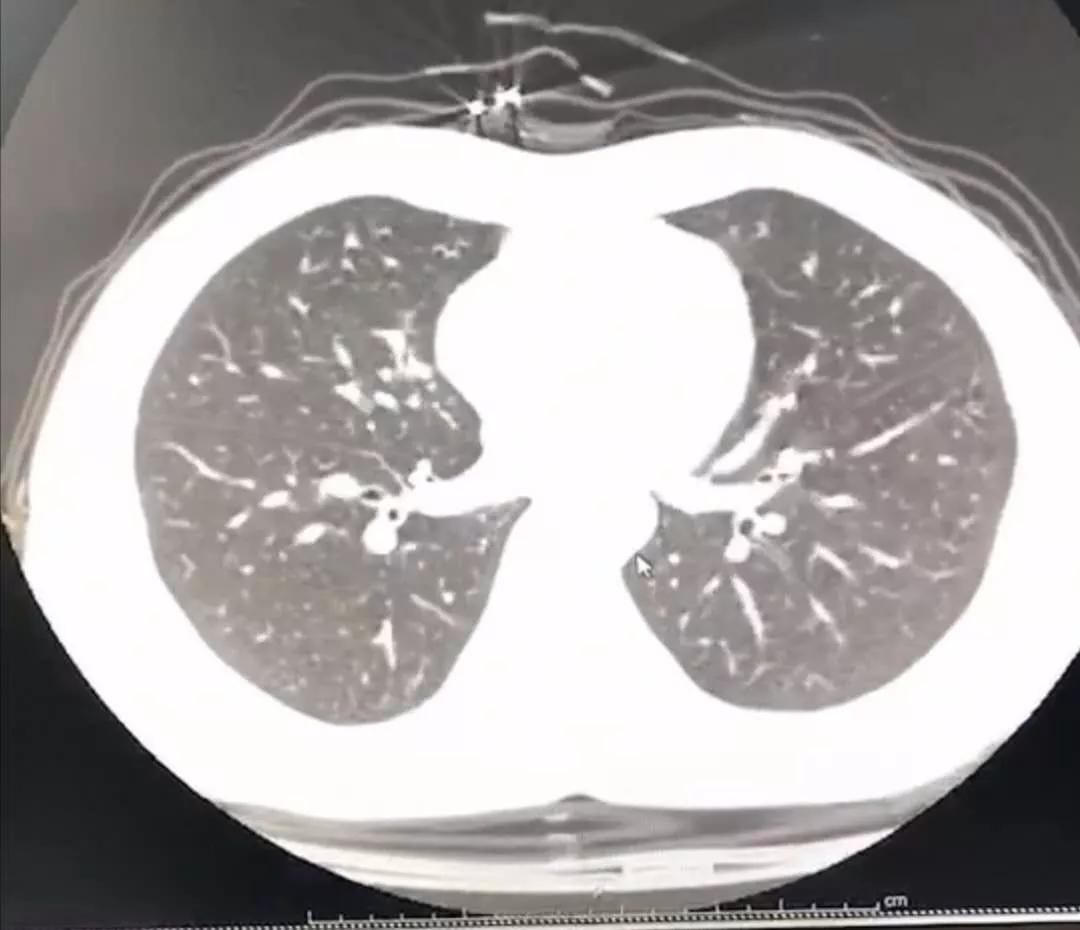

于是拖着沉重的步伐 , 周宁从家里出发去医院做胸部CT 。

幸运的是肺部还没有出现病毒性肺炎的特征性影像学表现 , 说明就算是新型冠状病毒感染 , 目前还属于轻型 , 没有实质性地累及肺组织 。